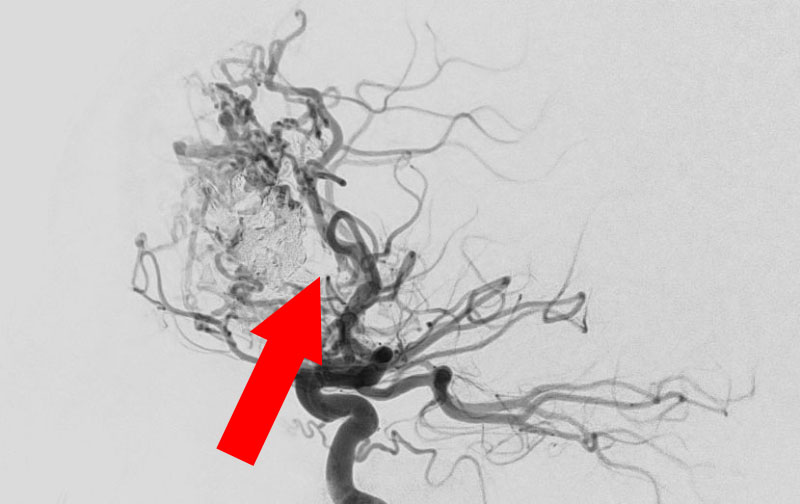

No.1583 手術前

No.1583 手術中

No.1583 手術後